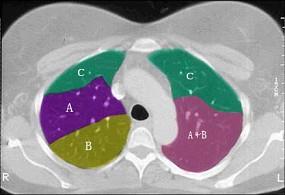

结合肺段模式肺动脉干与右肺动脉层面(见图),选出右肺中叶的组成 ( )A、D+EB、D+E+FC、B+CD、B+C+DE、B

问题 结合肺段模式肺动脉干与右肺动脉层面(见图),选出右肺中叶的组成 ( )

选项 A、D+E B、D+E+F C、B+C D、B+C+D E、B

答案 A